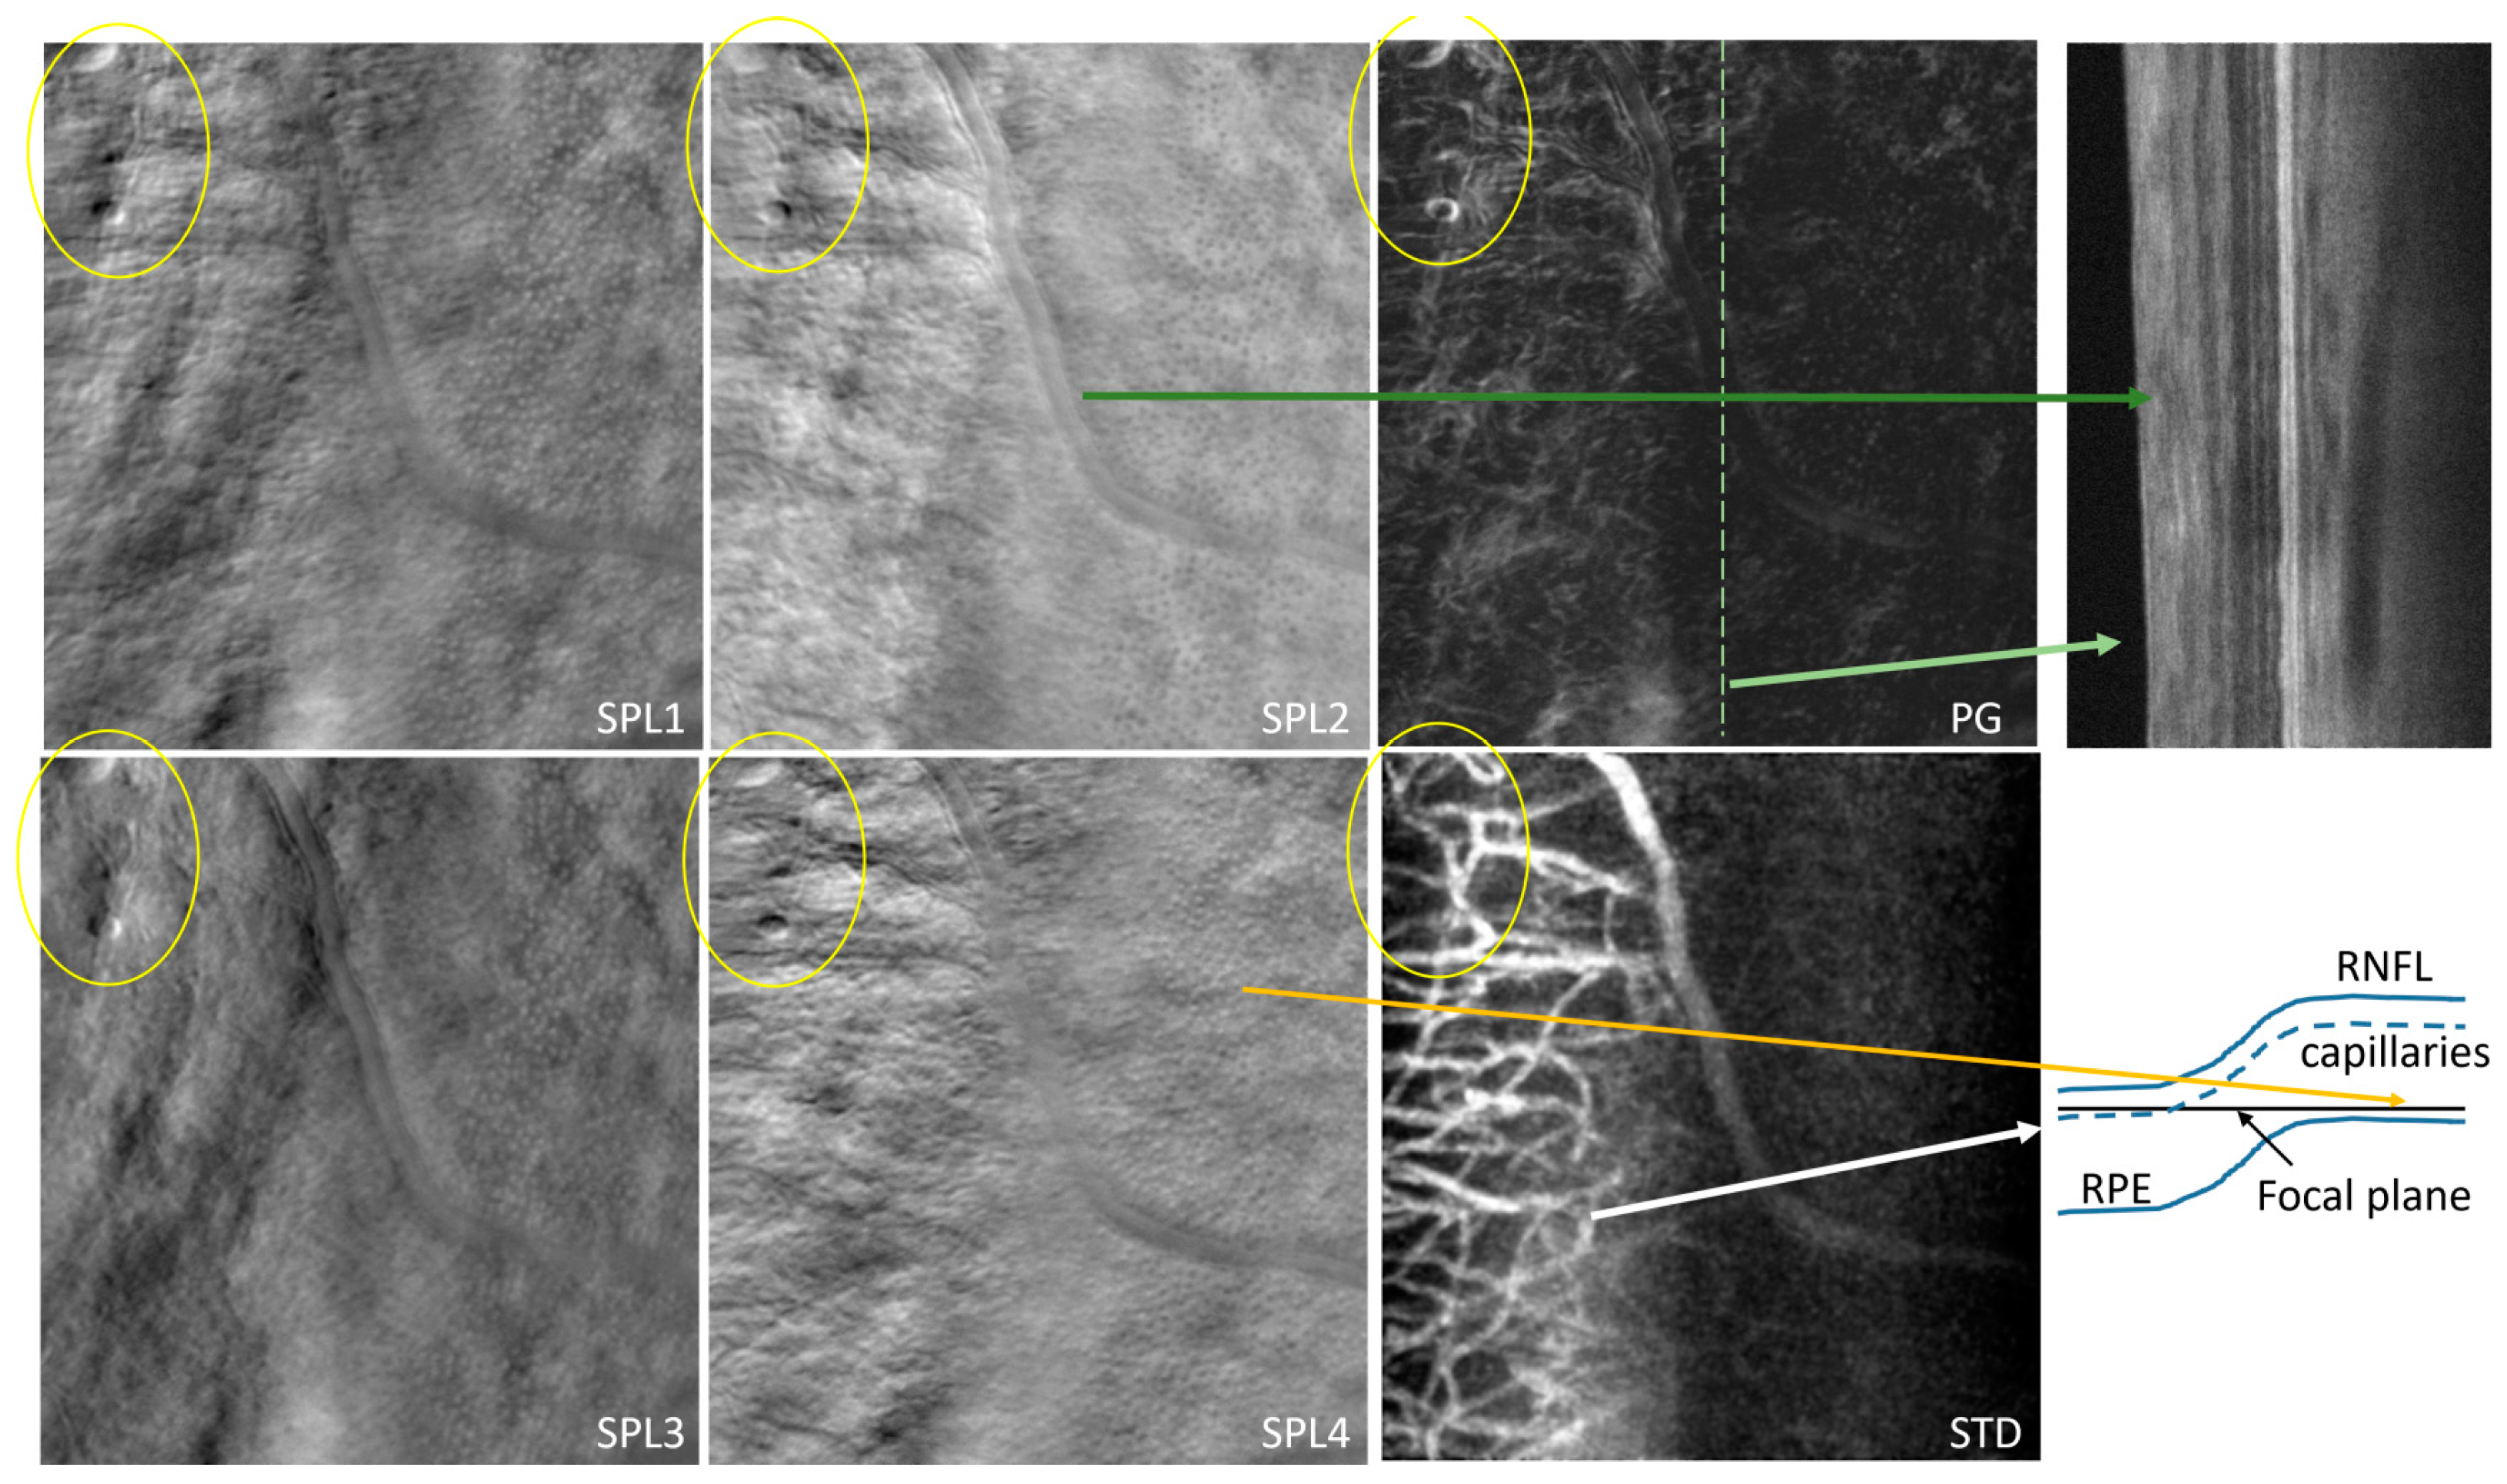

Figure 17 shows an example of the four offset images (O1–4) and the confocal (C) image simultaneously acquired with the OCT B-scan from a healthy subject. Figure 18 shows all the images derived from these four offsets: SPL 1–4, S, STD, SD, P, and PG. Figure 19 and Figure 20 show the images from glaucoma patients obtained at NYU with the upgraded CAORI (with flying-spot SLO and fiber bundle multi-offset detection).

A third version of CAORI has been converted to the flying-spot AO-SLO configuration, and the detection module consists of the fiber bundle simultaneously acquiring the confocal and the four offset channels, as in MAORI. Figure 17 shows an example of the acquired images (C and O 1–4), and Figure 18 shows the derived images (SPL 1–4, SD, PG, STD, and S). It should be noted here that SD, STD, S, and PG are all isotropic, direction-independent, as they were derived from all four offset images and are, therefore, directionally diverse. STD extraordinarily reveals the maps of capillaries with much better contrast than in any other imaging modality, in a mode similar to OCTA. STD can also be used to segment the flow location in large vessels and to quantify the inside diameter of the vessels. The complementarity of the derived images should also be noted in Figure 18. Some edges, like the vessel wall and some capillaries, are visible in some SPL images but not in others in the top row, while the bottom row shows all edges and capillaries in the isotropic images.

It is also important to note here that we can measure and quantify structures in these images. For example, one can measure in Figure 19 the inside (L) and the outside (D) diameter of a blood vessel [55]. The wall-to-lumen ratio((D-L)/2L) has diagnostic value [70,71,72], and with offset/split techniques, one can measure it in vivo with cellular-level resolution. We can see the detailed structure of the vessel wall, which is not possible with standard confocal imaging. The arrow in Figure 19 shows the local thickening of the vessel wall, which might indicate a potential future disruption. The circled area could be a cyst, a lipid deposit, or activated microglia approaching the injured location. Additional investigations are needed to confirm such a hypothesis, and multiple imaging sessions at the same location (not available in this case) would show if that round structure moves or changes in time. The right side of Figure 19 shows significant tortuosity in a glaucoma patient imaged with CAORI at NYU. Increased tortuosity of retinal vessels has been suggested as an indicator of arterial hypertension, retinopathy, cerebral vessel disease, stroke, and ischemic heart disease [73].

The images shown in Figure 20 are from a glaucoma subject imaged with CAORI at NYU. The patient has primary open-angle glaucoma of both eyes, mild stage, and ocular hypertension, bilateral. What is intriguing in this scan is the significant difference between the left and right sides of each image. The right side shows a very clear dotted pattern that resembles the cone mosaic (orange arrow) and no capillaries. The left side shows in the STD image a very distinct and sharply focused capillary vasculature that is usually located in the upper layers of the retina. The depth of focus in AO-SLO is generally very narrow (<50 µm); therefore, capillary layers and cones are not seen in the same image plane. One potential explanation is that the retina has a ridge laterally, as suggested in the sketch on the right side of Figure 20. This scenario can bring into focus different depths of the retina in different parts of the image. Additional investigations at the same location, such as an OCT volume scan (not available), are needed for clarification. Nevertheless, the encircled microstructures are also interesting, and potential correlation with the clinical diagnosis is of interest. The only available OCT image for this scan is shown at the top right of Figure 20, and its location is indicated by the dotted line in the PG image. The darker green arrow shows a large blood vessel in the RNFL running along a portion of the OCT scan.

As described in detail in [55], split-detection analysis, sometimes called differential phase contrast, is interpreted as phase derivative. One can reconstruct the phase from these derivatives or directly calculate the phase gradient. In our imaging configuration, split-detection analysis is performed using multiple combinations of the four offset images. Two orthogonal split (SPL) images are generated for orthogonal fiber pairs 1–3 and 2–4 (SPL 1 and 2). Two additional SPL images (SPL 3 and 4) are obtained by adding first adjacent fibers and then performing subtraction divided by the sum of the two added images. Therefore, we obtain four SPL images, two for horizontal and vertical directions and two diagonal (+/−45 deg). Each of the four SPL images highlights structural edges such as blood vessel walls along different directions given the directionality associated with the split (offset) direction. The phase gradient (PG) images are obtained from either one of these two pairs of SPL images. Standard deviation (SD) among the four simultaneous offsets [26] highlights the differences among these images, which are predominant at the blood vessel walls, due to the detection directionality diversity. The sum of all four offset images (S) combines all detected scattered light in a ring-detection configuration while rejecting the direct backscattered light detected in the confocal image through the central fiber (SLO or C). In addition, a mean of the four split stds (STD) is calculated, isotropically highlighting the blood flow vasculature as motion contrast.